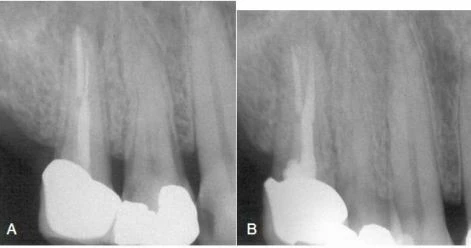

Hình 8. A, Dụng cụ gãy ở gần chóp của chân ngoài răng cối nhỏ hàm trên. B, Hoàn thành việc điều trị lại. Mảnh dụng cụ được băng qua bởi dụng cụ trâm tay và được lấy ra bởi tay siêu âm và trâm nội nha.

– Việc loại bỏ mảnh gãy dụng cụ nằm ở sâu vẫn có thể thực hiện bằng kỹ thuật siêu âm nếu có thể đưa dụng cụ băng qua mảnh gãy được. Hình 14-46 cho thấy lộ trình tháo mảnh gãy nằm sâu ở ống ngoài răng cối nhỏ hàm trên. May mắn là hình dạng ống tủy cho phép các trâm nhỏ băng qua mảnh gãy và cuối cùng mảnh gãy được tháo ra bởi một trâm nội nha và tay khoan siêu âm. Sau đó, việc điều trị tủy được tiến hành thành công. Điều đáng tiếc là nếu mảnh gãy nằm trong ống tủy có đường kính nhỏ hơn dụng cụ thì hiếm khi có thể đi băng qua mảnh gãy được. Việc dùng lực quay mạnh càng khiến cho dụng cụ dễ gãy hơn là cải thiện được tình hình. – Dụng cụ siêu âm bản thân nó cũng có thể bị gãy, đặc biệt là với những trâm số nhỏ. Điều quan trọng là giữ cài đặt năng lượng ở mức được đề nghị. Thông thường mảnh gãy sẽ được làm lỏng và trôi ra ngoài xoang tủy mà ta không phát hiện ra cùng với nước bơm rửa. Kết quả tương tự đạt được khi sử dụng đầu siêu âm được thiết kế đặt biệt cho việc mài mòn. Nếu như có thể băng qua mảnh gãy, kỹ thuật lấy cũng tương tự như lấy mảnh gãy trâm NiTi. Nếu dụng cụ siêu âm bị gãy thì nó thường xảy ra vào phút đầu tiên sử dụng thiết bị. – Khi loại bỏ mảnh dụng cụ gãy ở răng nhiều chân, một vấn đề có khả năng xảy ra là mảnh gãy trôi ra khỏi ống tủy và tìm đường vào những lỗ tủy khác. Để tránh điều này xảy ra ta nên đặt gòn vào miệng những lỗ tủy khác hoặc hoàn thành việc trám bít ở những ống tủy khác trước miễn sao đảm bảo các ống tủy còn lại không có sự thông thương với ống tủy bị nghẽn. – Kỹ thuật lấy mảnh gãy nhỏ ở 1/3 chóp hoặc ở đoạn cong nhiều của ống tủy không chỉ khó mà còn có nguy cơ làm mỏng thành ống tủy nếu như nó không gây xuyên thủng. Việc tháo mảnh dụng cụ mà không thể đi băng qua nó được là một vấn đề khó. Các kỹ thuật mới dùng thiết bị siêu âm để đào dưới kính phóng đại mà không có nước bơm rửa cũng cho thấy thành công trong việc bộc lộ một phần mảnh trâm gãy mà không làm gãy nó. – Khi tiến hành việc đào sâu vào chân răng song song với mảnh dụng cụ đòi hỏi phải xem xét giải phẫu ống tủy. Để tránh tình trạng thủng thành, an toàn nhất là đào ở vùng mô răng dày nhất. Đối với chân ngoài gần của răng cối lớn hàm trên, vùng an toàn nhất để đào là phía khẩu cái ống tủy ngoài gần; tuy nhiên, cần một đầu nội nha với đường kính vô cùng nhỏ (hình 9).